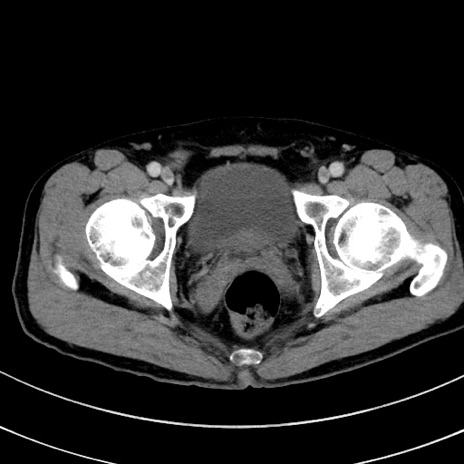

冠状断像

【症例】 60歳代男性

【主訴】 黒色吐物

【現病歴】 4日前から嘔気自覚、2日前の朝食後にも嘔気あり、自分で手で嘔吐反射起こし嘔吐したところ血が混ざっていたため受診。

【既往歴】 5年前汎発性腹膜炎を伴う急性虫垂炎で手術、高血圧、前立腺肥大症、高脂血症

【身体所見】 腹部正中に手術癩痕あり 腹部平坦・軟圧痛なし膨満感あり

【データ】WBC 8400、CRP 4.54